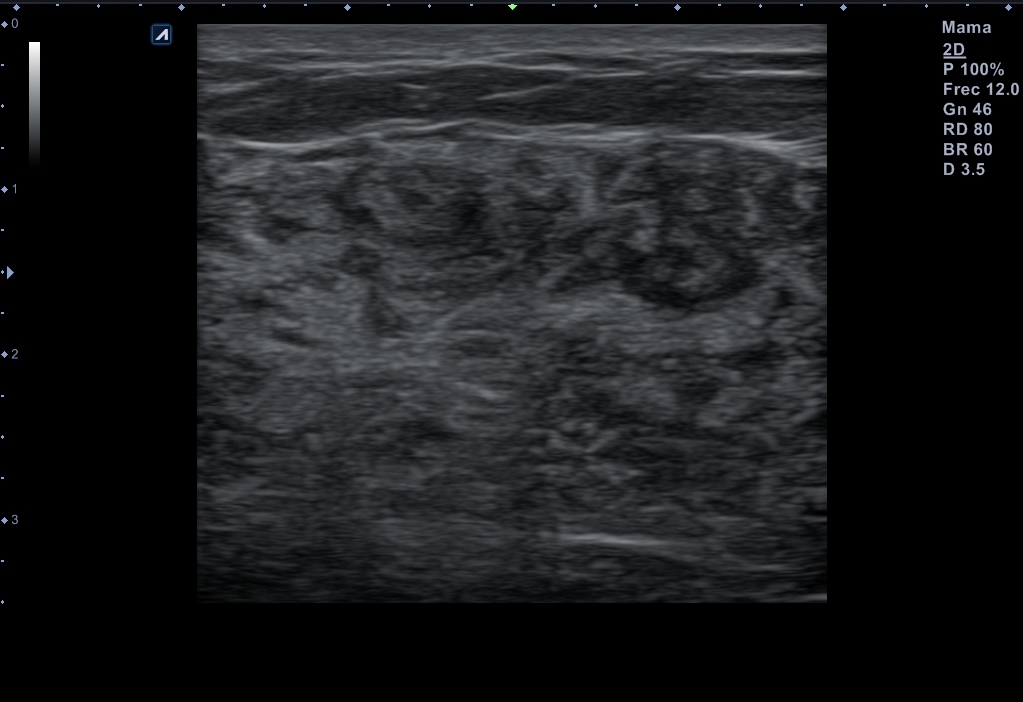

Se explora ambas mamas con ecógrafo con sonda lineal que muestra glándulas mamarias congestivas sin hallazgos patológicos.